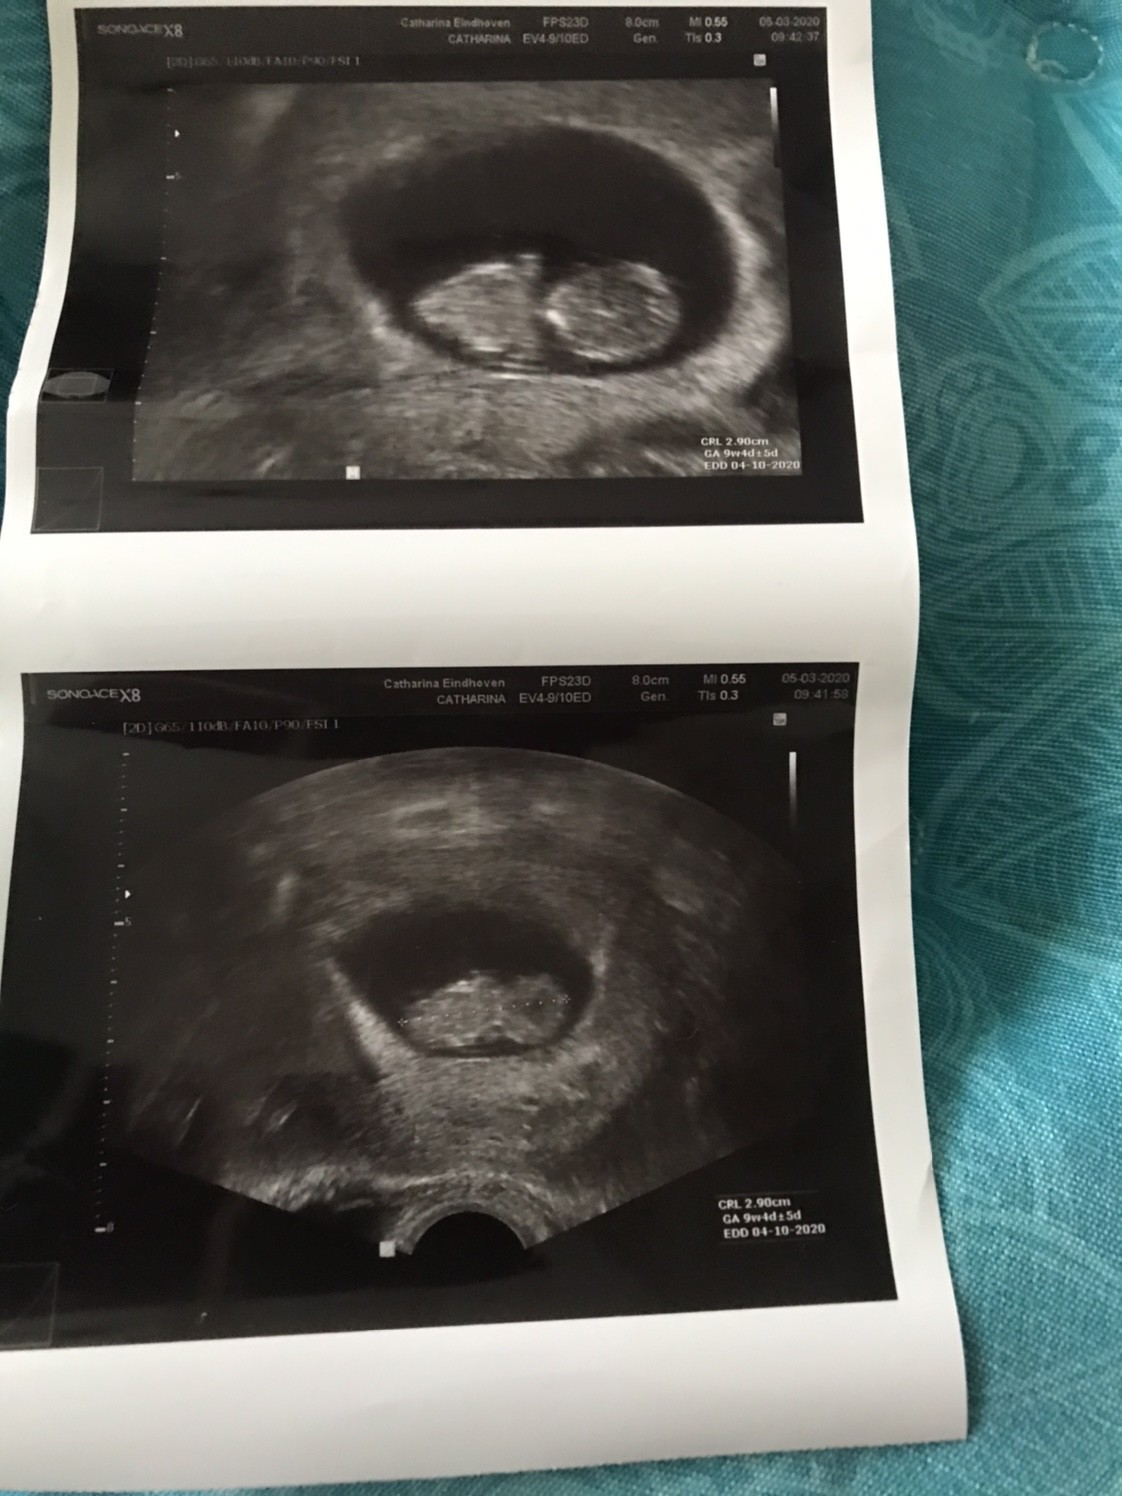

Dziewczyny w końcu dotarłam do domu. A wiec na dzień dzisiejszy wszystko jest dobrze. Maluszek ma nóżki i raczki, kręgosłup i szczękę - i oczywiście serduszko [emoji3059]

Po naciśnięciu ręka brzucha maluszek się ruszał a tak to spał.

Mamy 2,90cm i jest to 9+4 (wg om 9+5)

Termin porodu wpisany w zaświadczenie o ciąży 4.10.2020

A to nasz model/ka